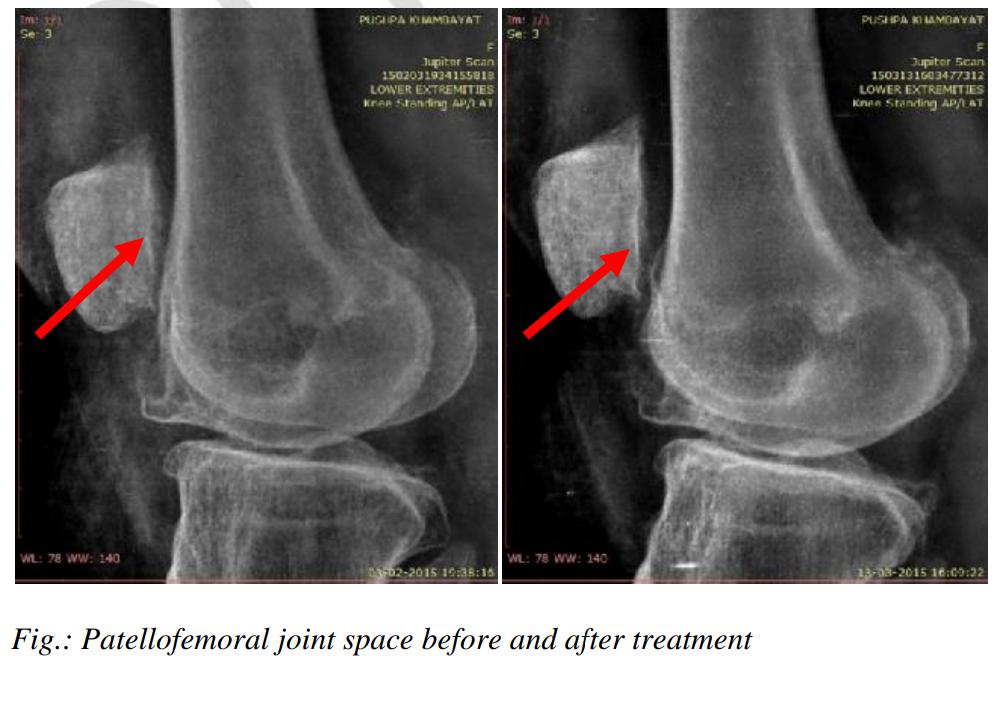

Chronic Osteoarthritis of the Knee is all about Improving Joint Space width. In a first of its kind study in the world, we have proven that it is possible to reverse JOINT SPACE WIDTH (JSW) between the Femur (thigh bone) and Tibia (Leg bone) in order to improve complications and symptoms of Osteoarthritis Knee. Traditionally, all Treatment give to an Osteoarthritic knee is focussed on Symptomatic relief of Pain/Swelling, while Scientific studies have focused only on regrowing Cartilage at the knee. We give you Images of patient's X-rays (with permission) to show you that Knee Osteoarthritis is fixable without Surgery.

Similar images from Osteoarthritis Knee Study

Eg.: Osteoarthritis is a degenerative condition for which Medical texts say that there is no cure. But through Clinical research studies, we have shown that Osteoarthritic changes in the Knee (like Joint Space Width and Osteophytes) can be reversed through aggressive Physiotherapy treatment. Such patients, once discharged from our care are scheduled once a month (or once in 6 weeks) to ensure that the patient is compliant with the exercise program and there is no reversal of Osteoarthritic changes. See X-rays below.

In the above images - one can see the Patellar Joint Space Width change in an Osteoarthritic knee, after Physiotherapy treatment. What you may find interesting is, that these images were taken in unilateral standing (standing on one leg). The Joint Space Width did not collapse despite standing on one leg.